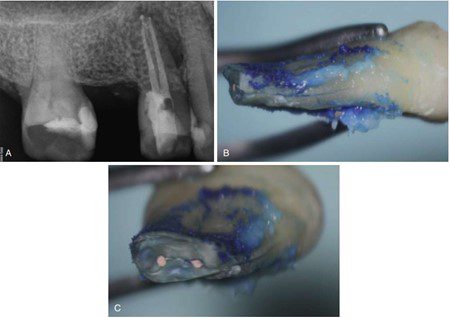

Trong các ống tủy rất lớn, có thể sử dụng côn phụ lớn hơn và cây lèn cỡ lớn hơn. Cần thận trọng trong quá trình lèn ngang, tránh tạo lực quá mạnh trong ống tủy (khuyến cáo này cũng áp dụng cho các kỹ thuật khác). Lực sử dụng được khuyến nghị không quá 2,5 pound để làm tránh gãy chân răng theo chiều dọc (hình 14.18).